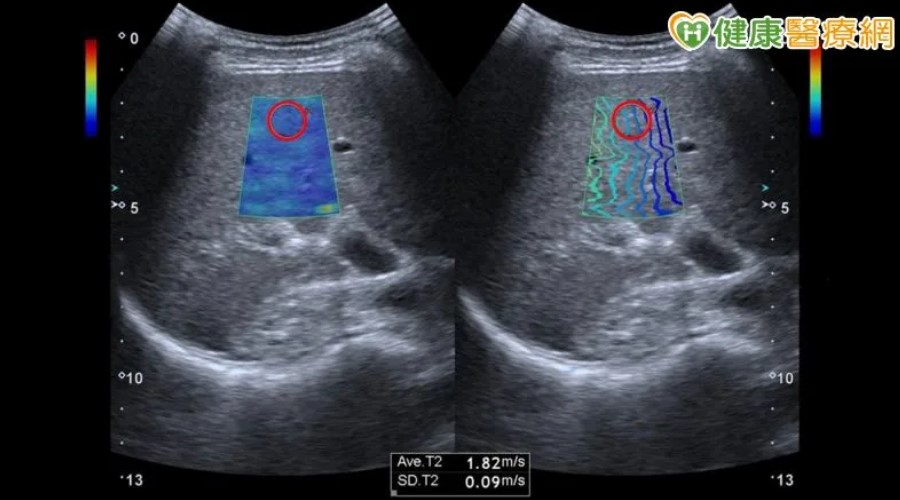

張女士很擔憂肝臟問題,今年6月安排至永越健康管理中心接受全身健康檢查,在檢查項目-肝纖維化及脂肪肝量化分析掃描(聲波脈衝成像超音波掃描ARFI),意外呈現重度纖維化,進一步至腸胃科葉勇呈醫師門診評估,醫師發現張女士並無B肝、C肝,亦無酗酒問題,因此搭配詳細的抽血及影像檢查,最後確診為原發性膽汁性膽管炎(Primary Biliary Cholangitis,簡稱PBC)

而血液生化及影像檢查是非侵入性的輔助檢查方式,過去醫師診斷纖維化或肝硬化,會幫病患掃腹部超音波檢查,肝臟影像如果比較粗糙或不規則,可能代表出現纖維化狀況,但粗糙的判斷非常主觀且無法精確評估嚴重程度;而肝臟纖維化的掃描檢查,同時可將肝臟纖維化定量化,如:聲波脈衝成像超音波掃描(ARFI)或肝纖維化掃描儀(Fibroscan);另外核磁共振彈性成像(MRE)也可以提供肝臟纖維化程度的評估,但費用昂貴。

個案張女士健檢時,透過肝纖維化及脂肪肝量化分析檢查,檢測聲波傳導數值為1.82m/s,結果顯示為重度肝纖維化。(無明顯肝纖維化<1.54m/s、中度肝纖維化≧1.54m/s、重度肝纖維化≧1.78m/s、肝硬化≧1.87m/s)